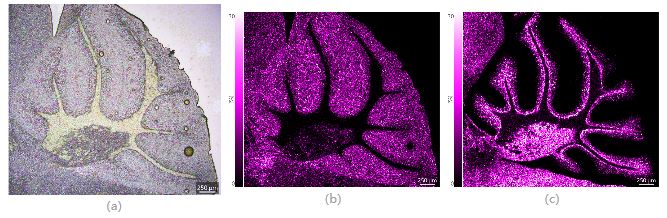

圖3 小鼠腦切片(整體)光學(xué)圖像及質(zhì)譜圖像 (a) 光學(xué)圖像;(b) PI(38:4)的質(zhì)譜圖像;(c) Sulfatide (C24:1)的質(zhì)譜圖像,空間分辨率15μm

對小鼠全腦切片(約17mmx9.4mm)進行分析,空間分辨率為15μm,檢測區(qū)域包含1126x624共702,624個像素點,檢測時間約6小時。